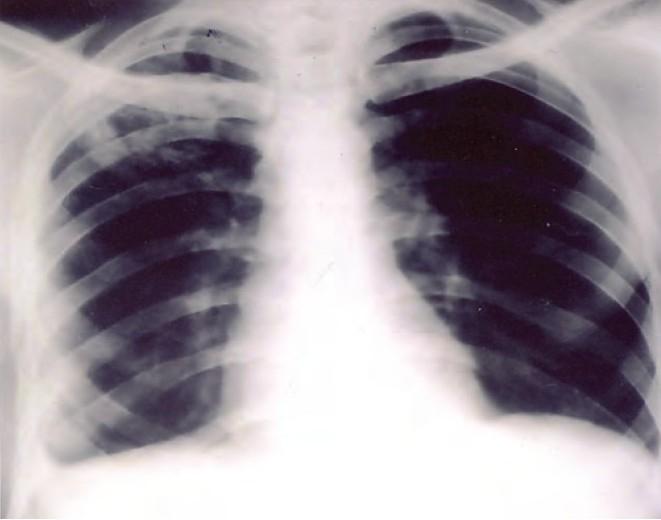

A 24-year old male developed left sided pleural effusion 10 days after the start of anti tubercular chemotherapy for right-sided pleural effusion and parenchymal lesion. This effusion seemed to be a paradoxical response as it resolved on follow up.

一名24岁男性在开始针对右侧胸腔积液和实质病变进行抗结核化疗10天后出现左侧胸腔积液。这种积液似乎是一种反常反应,因为在随访中它自行消退了。